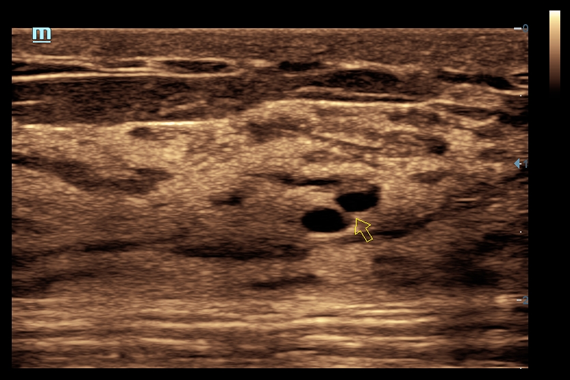

• iNeedle™ - улучшенная визуализация игл при проведении биопсии линейными датчиками

• Natural Touch Elastography - опция оценки эластичности ткани (эластография), с программой анализа. Действует на линейных датчиках 7L4A, L14-6NE и L9-3E